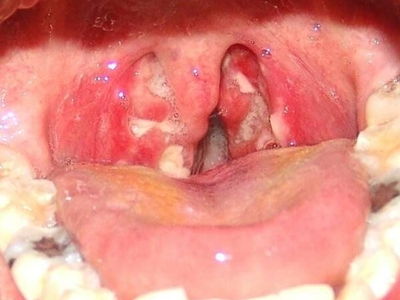

扁桃体癌属于扁桃体恶性肿瘤,为口咽部常见恶性肿瘤之一,病因可能与烟、酒等因素有关。本病可引起咽部不适、异物感、疼痛感、溃烂、出血等症状,临床常通过活检进行确诊,临床多采取手术切除治疗。

扁桃体癌通常先表现为咽部不适、异物感,随后咽痛加剧,可出现吞咽困难。同时,检查可见扁桃体肿大,表面溃烂,呈结节状隆起,易出血,可与周围组织粘连。